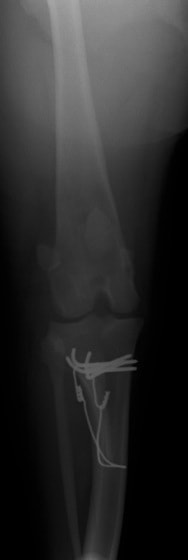

■ 症例20 ポメラニアン 8ヶ月 1.8kg

左右膝蓋骨脱臼 グレードⅢ

2ヶ月前から間欠的跛行が認められ、両膝の膝蓋骨脱臼整復術を行った。

手技は縫工筋及び内側広筋の解放、脛骨粗面の外側転位、滑車ブロック形造溝術、内外側関節包の縫縮を選択し実施した。

右側の膝蓋骨脱臼は上記手技で整復されたものの、左側はそれのみでは膝蓋骨が浮く様子が認められた。その為、PDS縫合糸にて膝蓋靱帯を1糸のみ縫合し、靱帯の縫縮を行った。

膝蓋骨脱臼は膝関節における膝蓋骨の内外側の脱臼と定義されるが、時として単純な内外の脱臼ではなく、膝蓋骨が大きく前方に浮き上がるように脱臼する場合がある。特にトイプードルやポメラニアンといった犬種に多く認められる。

内側脱臼に加えて前方への浮き上がりを矯正する為に、従来より脛骨粗面転移により膝蓋靭帯を外方と下方に引っ張り、固定する方法を選択する。膝蓋骨の前方への浮き上がりが軽度の場合は、従来法ではなく関節包の縫縮で対応していた。しかし、一部の症例で膝蓋骨の動きが悪くなり伸展機構が円滑に機能せずロボット様歩行になるケースがあった。

その為、膝蓋靭帯自体を縫縮する方法を採用した。この方法により、膝関節の伸展機構を妨げず膝蓋骨の軽度の浮きを矯正することが可能となった。

本症例の経過は良好である